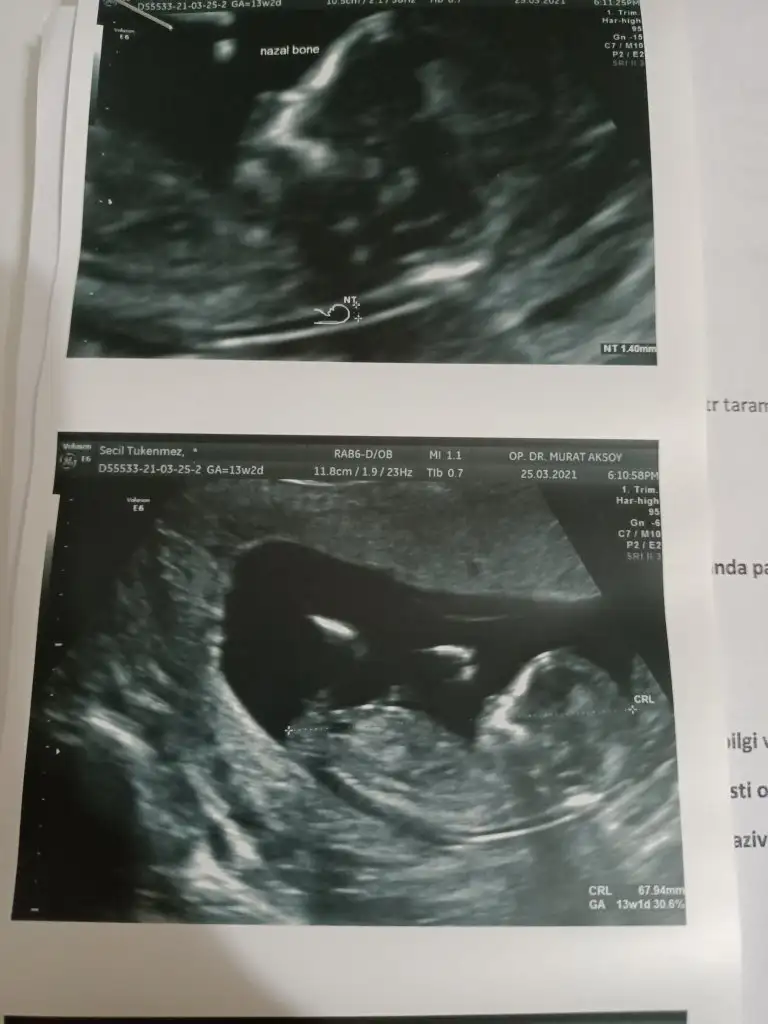

İkra meyra Sizce cinsiyeti nedir 13 hafta

• 20210324_193117.webp

20210324_193117.webp

20,7 KB · Görüntüleme: 85